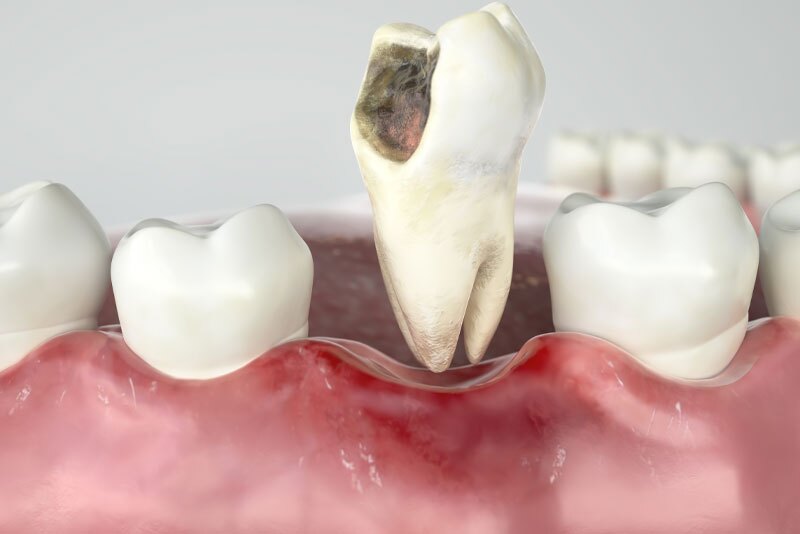

The decision to perform an extraction is typically straightforward when a tooth is impacted by significant decay, severe periodontal disease or a fracture. In addition, impacted wisdom teeth nearly always need to be extracted. Digital X-rays are used to analyze the underlying structures and determine if the tooth can be saved. If there is a pulp infection without a tooth fracture, root canal therapy is a highly successful method for preventing extraction. Extraction of normal teeth may be required for orthodontics, full mouth dental implants or when a primary tooth hasn’t fallen out and is stopping a permanent tooth from erupting. At Kari Mann Dental Studio in Cape Coral, our goal is always to save natural teeth, however, if conservative treatment is ineffective, extraction may be necessary. Extraction of a damaged or abscessed tooth can prevent more serious issues from impacting other teeth, your oral health and even your physical health. Regardless of the reason, Dr. Kari Mann has extensive expertise performing gentle tooth extraction in Cape Coral, FL. With a local anesthetic and sedation if you need it, tooth extraction will alleviate acute or chronic tooth pain and restore your oral health.

Due to the position at the back of the mouth, lack of space or an obstruction, wisdom teeth (third molars) frequently become partially or completely impacted. Impacted wisdom teeth are hard to clean so they’re prone to bacteria buildup. This can lead to decay, pain, swelling, gum disease and cysts that can harm adjacent teeth and bone. Dr. Kari Mann offers wisdom tooth removal in Cape Coral, FL under local anesthesia and sedation, however, more complex cases may be referred to an oral and maxillofacial surgeon.